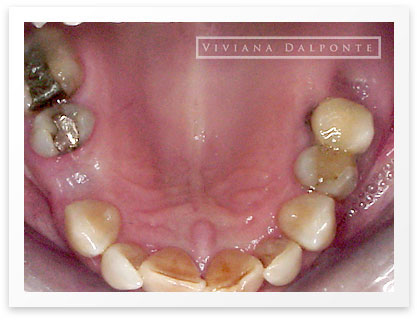

CASO 6: Restauración con prótesis fija en ambos maxilares